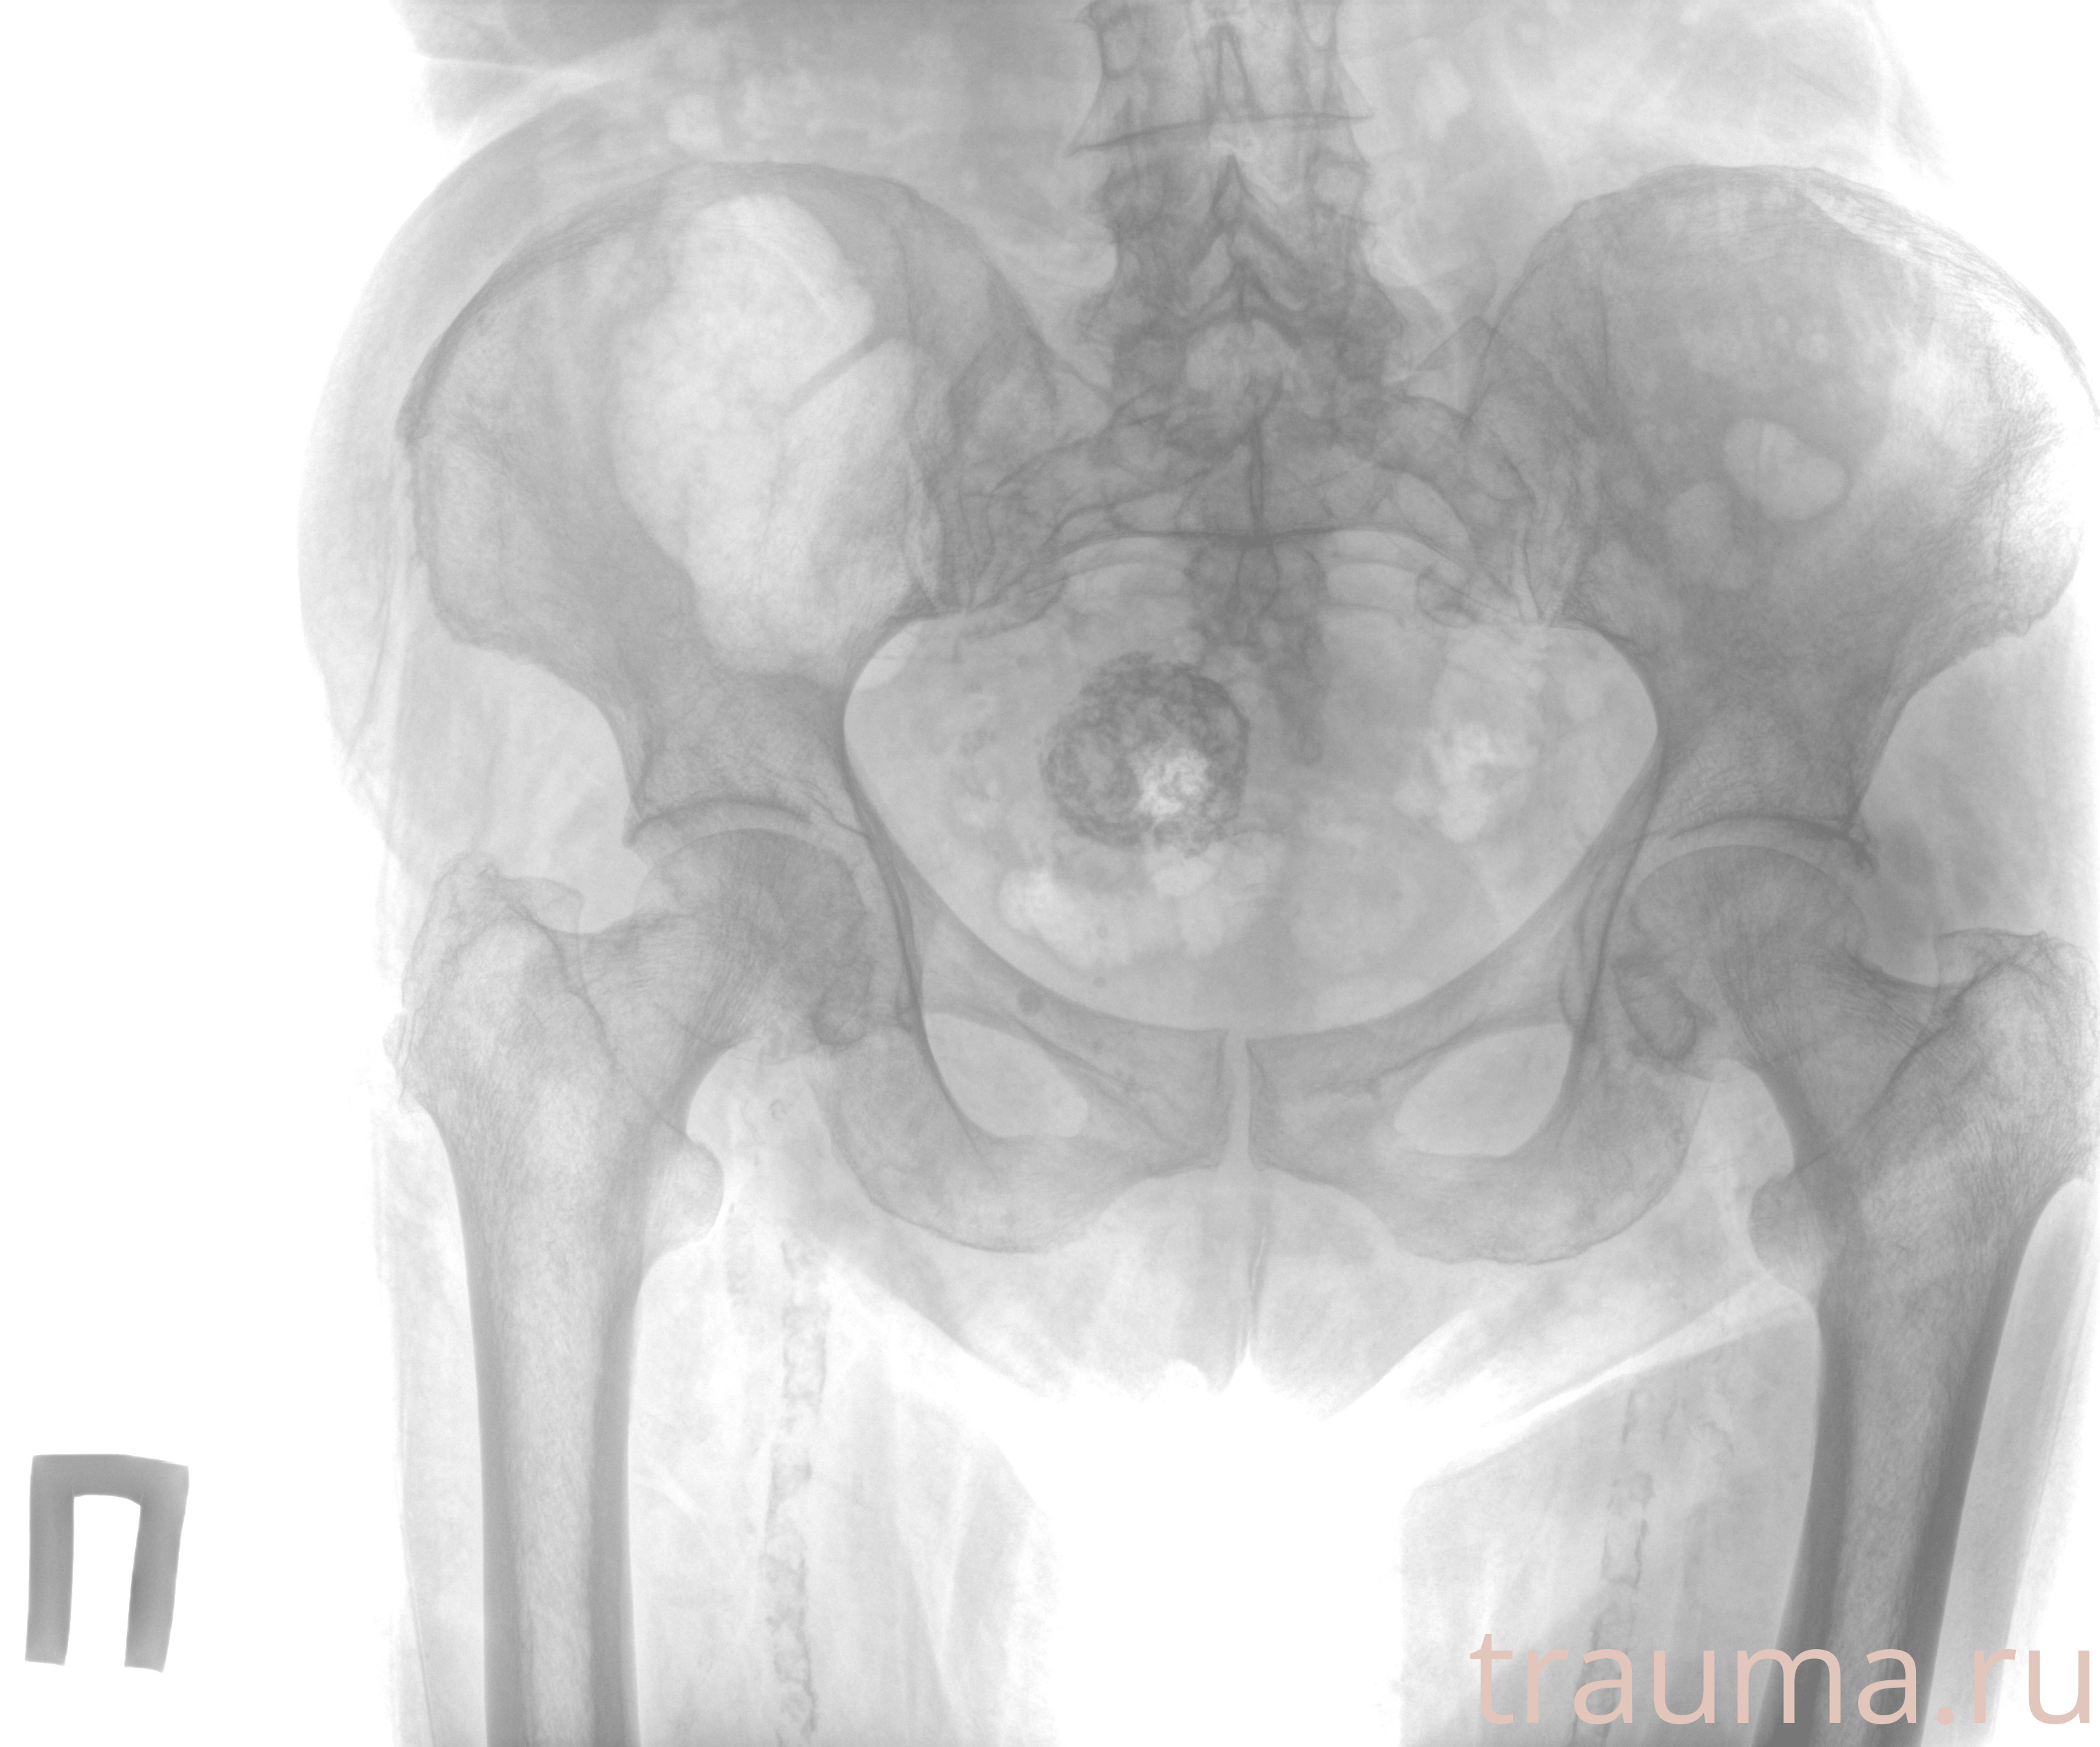

Рентгенограммы

Рентген на дому: по вашему адресу приезжает врач-рентгенолог, травматолог-ортопед с мобильным рентгеновским аппаратом, проводит диагностику травмы или заболевания, делает необходимые рентгенограммы, дает рекомендации по дальнейшему лечению. Получить качественные снимки в домашних условиях возможно благодаря уникальной методике, разработанной МосРентген Центром для института  Склифосовского

Яркость: 1   Контраст: 1   Инвертировать: 0 Увеличение: 1

Перетаскивайте мышь вверх/вниз для контраста, влево/право для яркости. Прокрутка колесом изменяет масштаб. Нажмите Сбросить для возврата к исходному изображению. При увеличении держите мышь в той области, которую хотите рассмотреть.